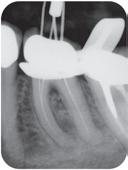

Høykonsentrert tyntflytende kalsiumhydroksidpasta med >41% hydroksid i en konsistens som enkelt appliseres med en liten og fleksibel plastkanyle: Flexi-Tip. Autoklavérbare Flexi-Tip i kombinasjon med den myke konsistensen sparer deg for tid, og hjelper deg å oppnå en presis og dyp applisering. pH 12,4 gjør den baktericid. Langvarig. Røntgenkontrast.

858,-

Calasept kalsiumhydroksid

Høykonsentrert kalsiumhydroksid på >41%. pH 12,4 gir høy antibakteriell effekt, bakteriedrepende. Røntgenkontrast. Langvarig. Klar til bruk, appliseres direkte gjennom steril kanyle.

Calasept EDTA

Skyllevæske til kjemisk utvidelse av rotkanaler. Letter den mekaniske utrenskningen. Leveres med adapter til skyllesprøyten.

Nå 250ml.

Calasept CHX

2% Klorhexidindiglukonat. Benyttes etter EDTA ved revisjonsbehandlinger og alle typer nekrosebehandlinger. Nå 250ml.

589,-